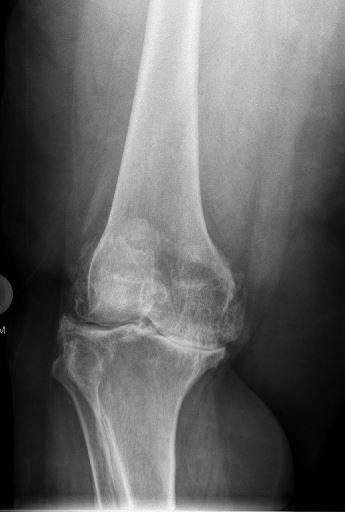

An x-ray of a total knee replacement before surgery

Before Total Knee Replacement